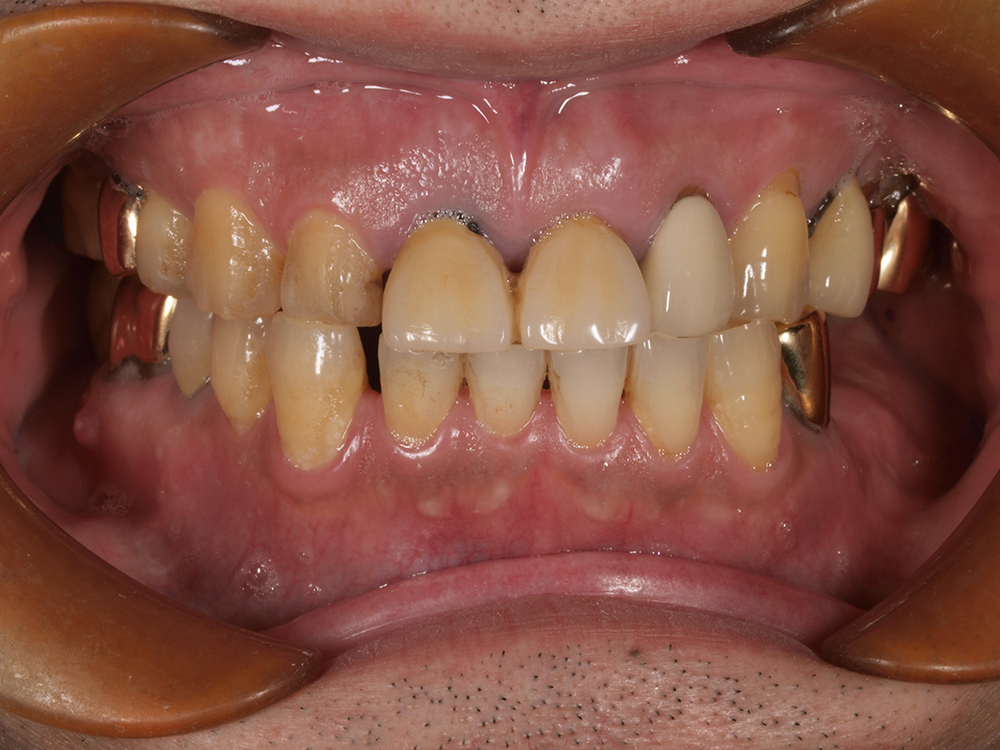

55歳 男性

- 主訴

- 前歯でしか咬めなく、食事を採るのに非常に困難で辛い

- 処置内容

- 上顎6本、下顎3本

- 治療費用

- 上顎:約230万(税込)下顎:約120万(税込)

- 治療期間

- 上顎:1年(仮歯まで8か月)下顎:8か月(仮歯まで5か月)

- リスク

- 上部構造物、仮歯の破折、術後の腫れ(3日)、人工歯根脱落リスクがあります